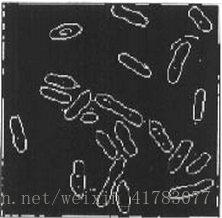

区域生长法是根据图像预先的先验知识和标准,利用初始点周围的生长提取出图像中的连接的区域。区域生长方法中通常利用图像的灰度信息,或者是根据图像的边界的信息得到其所需的标准。区域生长法中最简单的模型中,需要手动初始化,即选定一个点作为区域增长的起始点,然后基于一些预先定于的标准在初始点的邻域搜索,提取所有符合标准的像素区域。例如:一个常用的标准就是,提取初始点的邻域像素点直到遇到图像边界。如图1中所示,区域生长用于隔离图2中所示结构。

图2 区域生长法选取初始点